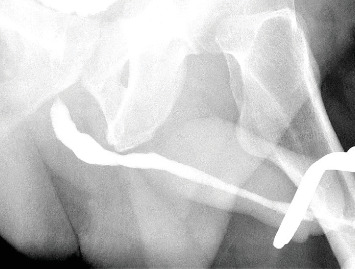

背景:男性尿道内自插入强力胶是一种罕见且具有挑战性的尿道阻塞原因,迄今为止仅报道了5例。这些病例表现出不同的临床表现和治疗方法。本文报道第6例记录病例,回顾现有文献,并提出一种结构化的治疗方法来治疗超胶粘剂引起的尿道梗阻。病例介绍:一名51岁男性在尿道内注入强力胶,以固定插入自我刺激的针尖梳。在强行取出梳子后,硬化的强力胶碎片仍然卡在尿道中,导致尿潴留。在局部麻醉下,采用刚性膀胱镜和镊子成功取出阴茎、尿道和膀胱内的所有碎片。结论:局部麻醉下采用刚性膀胱镜早期内镜下取出是治疗尿道非黏附性强力胶碎片的一种安全有效的方法。

Background: The self-insertion of superglue into the male urethra is an uncommon and challenging cause of urethral obstruction, with only five reported cases to date. These cases demonstrate diverse clinical presentations and treatment approaches. This report presents the sixth documented case, reviews the existing literature, and proposes a structured treatment approach for superglue-induced urethral obstruction. Case Presentation: A 51-year-old male instilled superglue into his urethra to secure a pintail comb inserted for self-stimulation. Upon forcefully removing the comb, hardened superglue fragments remained stuck in the urethra, causing urinary retention. Endoscopic extraction using rigid cystoscopy and forceps under local anesthesia successfully removed all fragments from the penile urethra and bladder. Conclusion: Early endoscopic extraction using rigid cystoscopy under local anesthesia represents a safe and effective treatment option for nonadherent superglue fragments in the urethra.